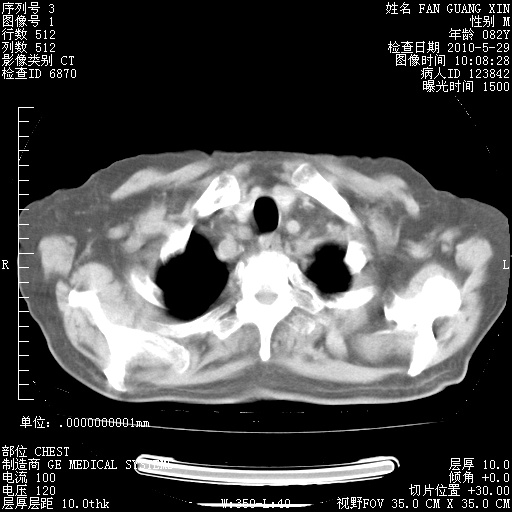

再治疗10天后的肺部CT

再治疗10天后的肺部CT 纵膈窗

阅读此次胸部CT,肺间质渗出性改变较入院时有吸收。目前从体温、白细胞、中性分叶明显增高,肯定存在细菌感染(发生医院感染哦,若无消化道及泌尿系统等感染的依据,肺部感染可能大)。若你院头孢哌酮舒巴坦钠耐药率较高,同意你的方案,若48小时体温仍高,可考虑使用碳青霉稀类抗菌药物,同时可予超声雾化、注意滴数时加大液体量。白蛋白33.30g/L较低哦,需加强营养等支持治疗。